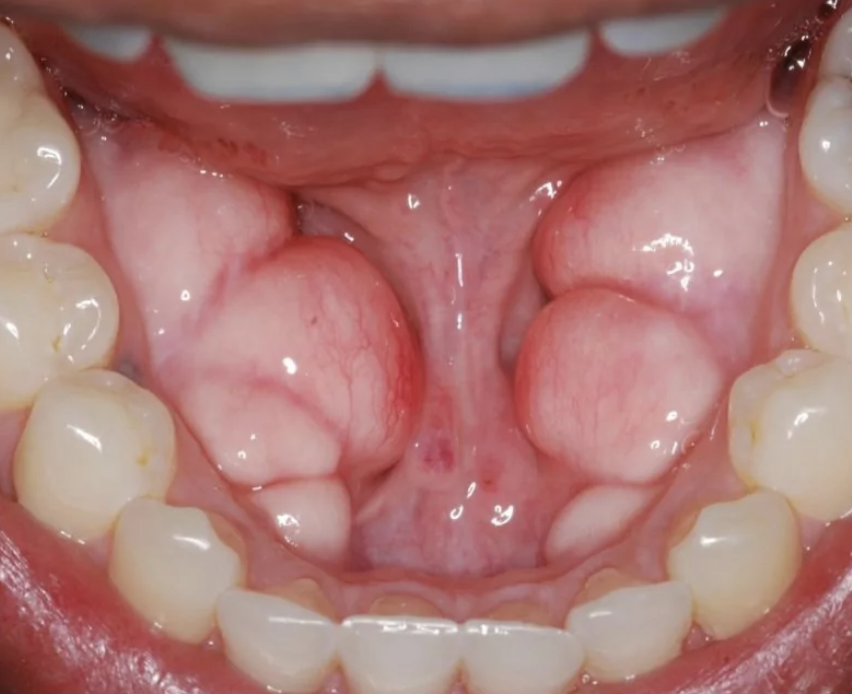

>>77143766

You see this picture? Which jaw would you say is the most attractive and masculine?

For me I'd say BD or KD

I am about OR or PE. That's what slight overbite means

I am 28 so there is no way I can get to even LE but fingers crossed